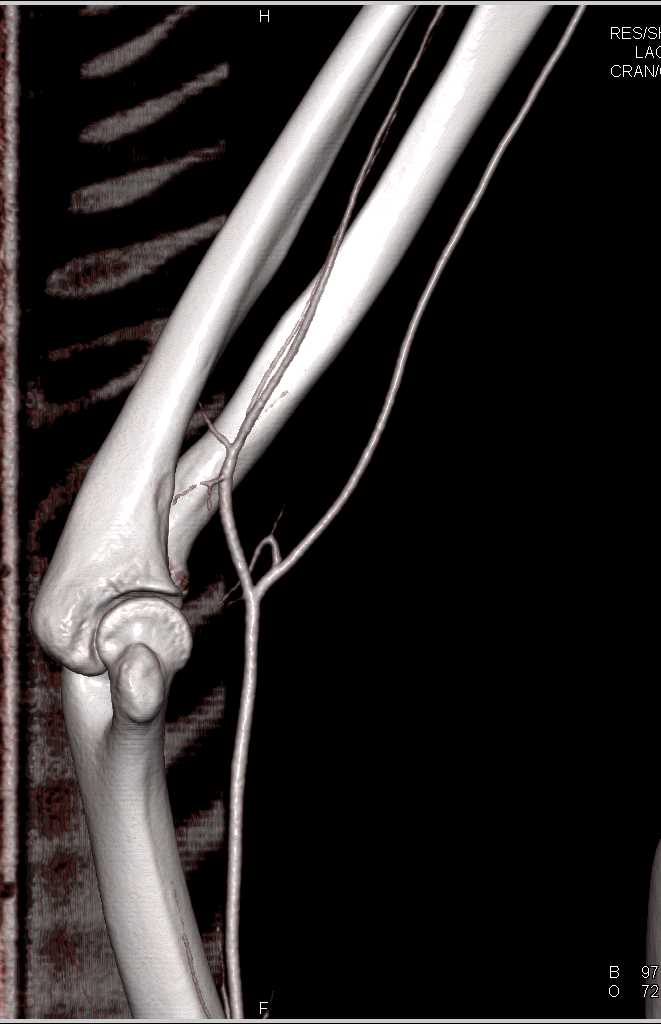

Soft Tissue Injury with Patent Vessels